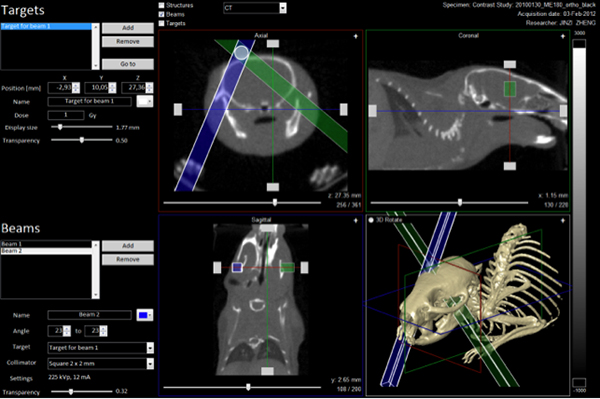

- Image-guided small-animal RT with the state-of-the-art XRAD-SMART IGRT platform

State-of-the-art small-animal IGRT platform allows small animals to be treated with a similar level of precision as those implemented on patients.

Our program collaborates with other BIRI faculty who are experts in imaging protocol development, and implements these novel protocols on patients who undergo radiation therapy to guide dosimetric planning design or monitor treatment response with longitudinal imaging. We also collaborate with biologists from BIRI and the regenerative medicine research program to implement the state-of-the-art small-animal IGRT platform as a BIRI core service, to significantly improve the quality and sophistication of small-animal radiation imaging and treatment.